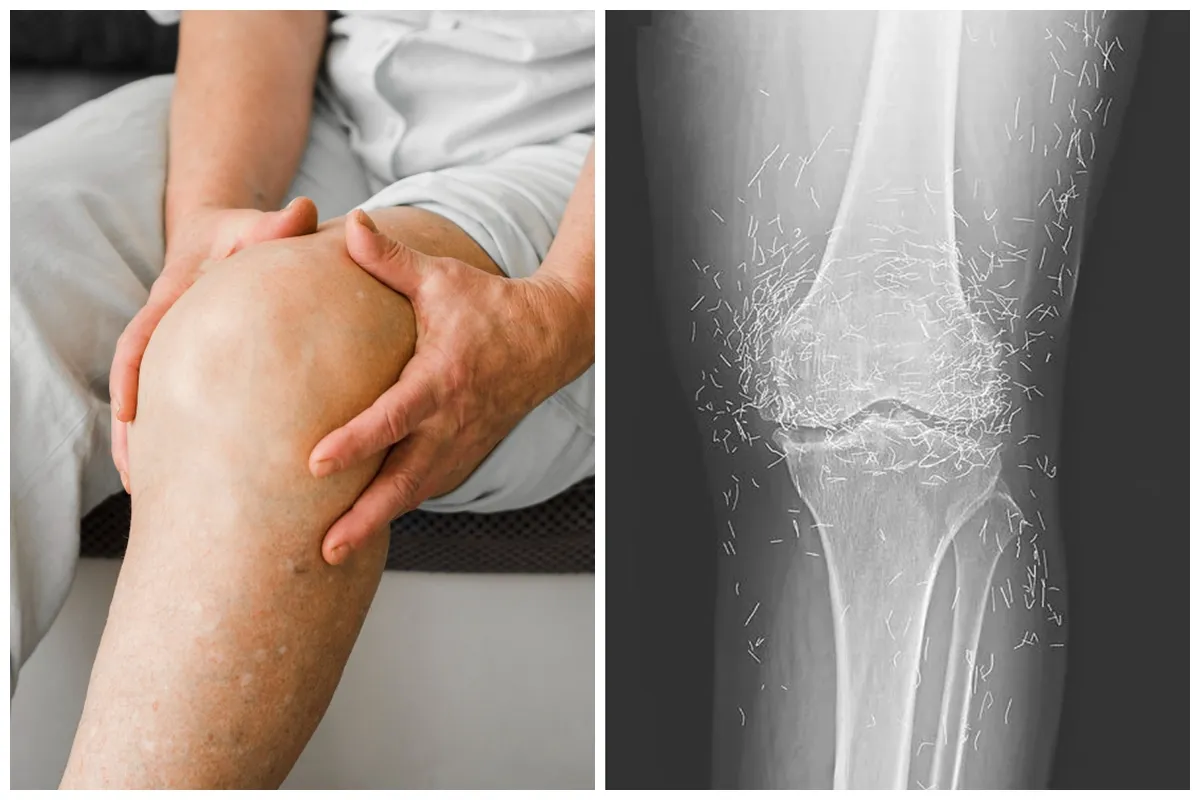

Pihak medis menjelaskan pasien awalnya datang ke rumah sakit dengan keluhan lutut yang terasa sangat nyeri. Setelah dilakukan pemeriksaan lebih lanjut, hasil rontgen menunjukkan adanya perubahan bentuk pada tulang kering bagian dalam lutut yang tampak menebal dan mengeras.

foto: The New England Journal of Medicine

Selain itu, pertumbuhan tulang kecil atau bone spurs juga muncul di sekitar sendi lutut. Pada saat yang sama, dokter melihat adanya bintik-bintik putih dalam jumlah besar yang ternyata merupakan benang emas.

"Ia kemudian datang ke rumah sakit karena lututnya sangat nyeri. Rontgen pada lutut kirinya menunjukkan tulang kering bagian dalam menebal dan mengeras. Ada juga pertumbuhan tulang kecil di sekitar tulang kering dan tulang paha dekat sendi lutut," imbuhnya.

Temuan mencengangkan muncul dalam hasil rontgen berikutnya. Ratusan benang emas terlihat jelas menempel di sekitar sendi lutut.

"Dokter juga melihat ratusan bintik putih pada hasil rontgen di sekitar sendi lutut, yang ternyata adalah benang emas kecil," ungkapnya.